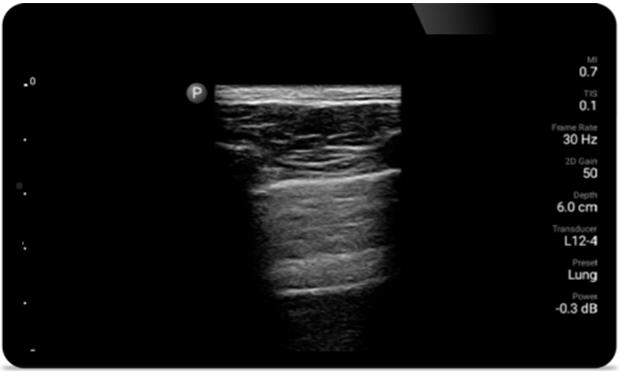

Lumify can help assess patients faster and improve accuracy when diagnosing common causes of dyspnea and other lung conditions.

• 4 to 1 MHz extended operating frequency range • 2D, color Doppler, M-mode, advanced XRES and multivariate harmonic imaging • High-resolution imaging for abdominal and cardiac applications: Cardiac, OB/GYN, Lung, Abdomen and FAST imaging preset optimizations Lumify aids life-saving technology in prehospital setting